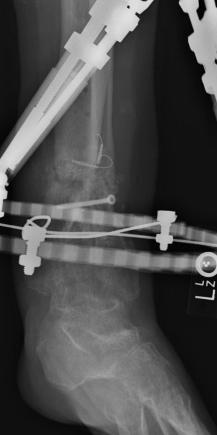

Postoperative (13th) images of left ankle

The image(s) displayed here were created following Liam's 13th surgery which was performed by Dr. Saunders. After a few hiccups getting

the surgery scheduled, Liam spent most of the September 13th afternoon in his 13th surgery. ;-) The surgery lasted about 5 hours and according

to the doctor, it was a good surgery. The 1st photo shows the new frame bracing that holds Liam's ankle together. The next series of photos show

various angles of the ankle and the rods that go from the frame into and through the left ankle. There was some concern that the swelling would

burst and allow for infection. Looks like we are now past that concern. Liam is still on antibiotics to ward of potential infection. The flesh

images show how the skin reacts to having the leg adjusted by the brace. The doctor has had to cut the skin to allow the rods to move freely.